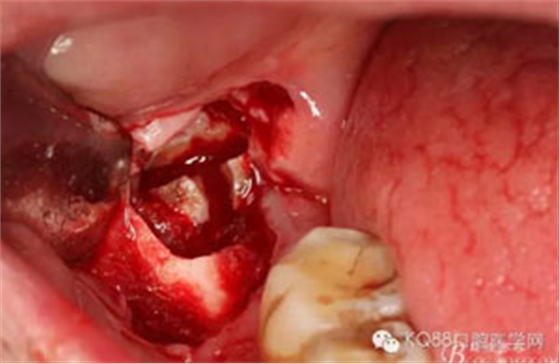

圖12. 先取出48牙冠

圖13.從頰側(cè)和舌側(cè)兩個方向用挺。挺出牙根

圖14.清理拔牙創(chuàng),并放置膠原蛋白海綿。